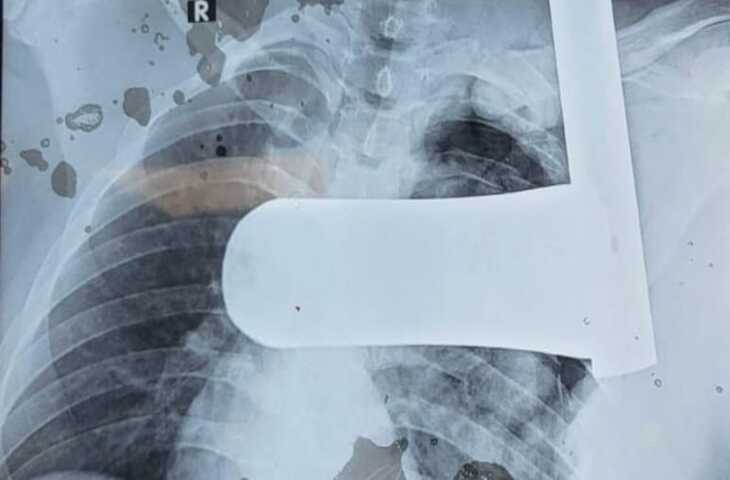

राजस्थान के उदयपुर से चिकित्सा जगत की एक हैरान कर देने वाली और राहत भरी खबर सामने आई है। RNT मेडिकल कॉलेज के डॉक्टरों ने जटिल सर्जरी कर भीलवाड़ा के एक युवक के सीने से 9 इंच लंबा लोहे का पाइप निकालकर उसे नई जिंदगी दी। इस चुनौतीपूर्ण ऑपरेशन को डॉक्टरों की बड़ी सफलता माना जा रहा है।

जानकारी के अनुसार भीलवाड़ा निवासी युवक गंभीर हालत में उदयपुर के RNT मेडिकल कॉलेज पहुंचाया गया था। युवक के सीने में लोहे का पाइप घुसा हुआ था, जिससे उसकी स्थिति बेहद नाजुक बनी हुई थी। मामला इतना गंभीर था कि जरा सी चूक जानलेवा साबित हो सकती थी।

अस्पताल पहुंचते ही डॉक्टरों की टीम ने तत्काल जांच कर आपात सर्जरी का फैसला लिया। विशेषज्ञ चिकित्सकों की टीम ने बेहद सावधानी और सटीक रणनीति के साथ ऑपरेशन शुरू किया। लंबे और जटिल प्रयास के बाद डॉक्टरों ने युवक के सीने से 9 इंच लंबा लोहे का पाइप सफलतापूर्वक बाहर निकाल दिया।